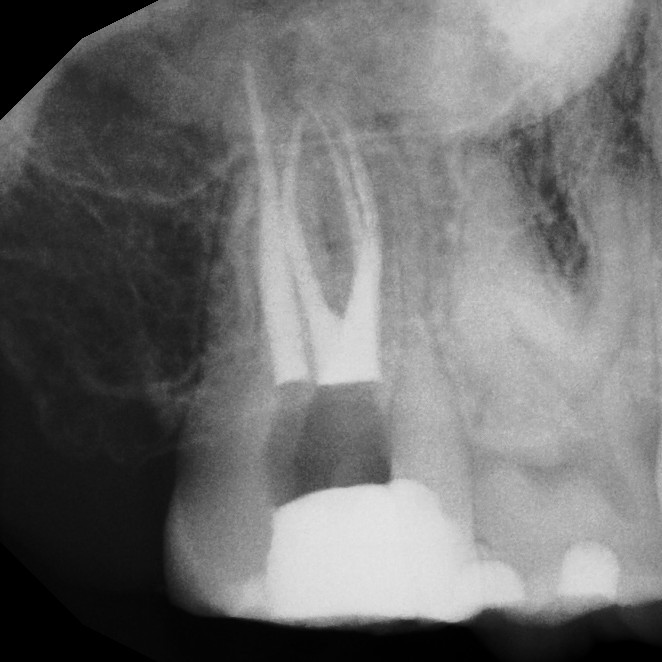

Retreatment

Sometimes, a tooth that has already undergone root canal therapy may not heal as expected or may develop new problems months or even years later. In these cases, endodontic retreatment offers a second chance to save the tooth. During this procedure, the existing filling materials are carefully removed from the canals, the inside of the tooth is cleaned again, and any hidden or untreated areas are addressed before the canals are sealed once more. This process allows your dentist to correct any issues and give the tooth the best possible chance for long-term success.

Thanks to modern tools and techniques, retreatment is a precise and effective procedure that can often be completed comfortably under local anesthesia. Many patients are surprised to learn that retreatment is no more uncomfortable than the original root canal. By choosing retreatment instead of extraction, you preserve your natural tooth, maintain your smile's appearance, and avoid the more complex and costly process of replacing a missing tooth.